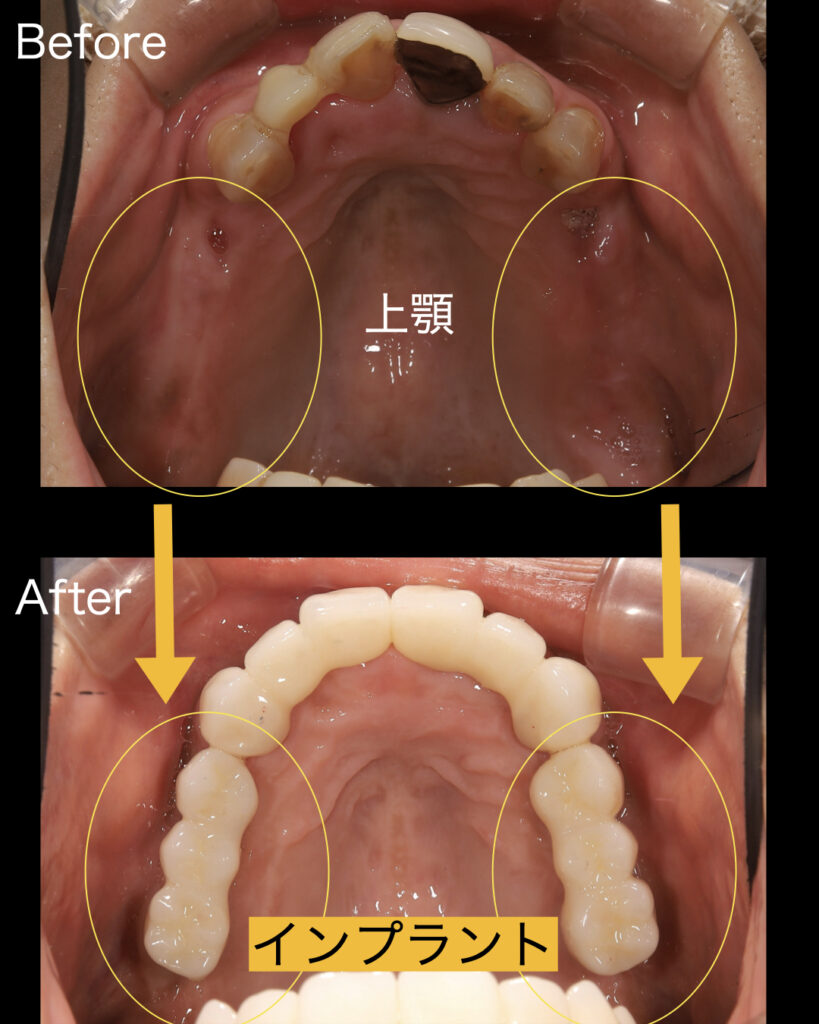

残念ながら下の前歯は歯周病により保存不可能な歯は数本抜歯させて頂きました。上の前歯は歯茎を整え根の治療を行えばまだまだ残せると判断し、根管治療を行いました。その間に左右の奥歯に大幅な骨造成(サイナスリフト)を行い、骨が硬化するまで半年ほどの治癒期間を設けました。その間に他の部位の治療と仮歯を入れました。

インプラント手術は下顎から行いました。上顎は骨がないので骨造成を行いましたが、下顎は骨が十分にあったため、他の治療と同時並行でインプラント埋入を行いました。

上顎の奥歯は骨造成サイナスリフトを行って6ヶ月待ったあとに、インプラント埋入を行いました。治癒経過もよく骨も硬くなっていたので、通常通りインプラント埋入を行えました。まずは右側を行い、その後に左側、2ヶ月ほどで生着がみられたので仮歯を入れ噛めるようにし、噛み合わせ、頬や舌を噛まないか、見た目などの審美的な面もすべてチェックを行いました。問題がないことを確認したあとに最終的なインプラントの上部構造であるセラミックをセットすることができました。